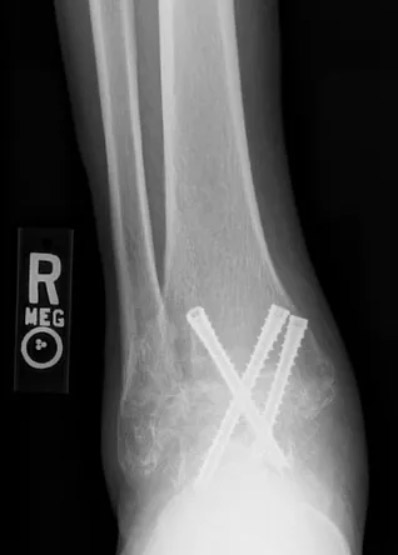

Example of an ankle fusion procedure performed by Dr. Anthony Yi.

X-ray's of the same ankle before undergoing ankle fusion.